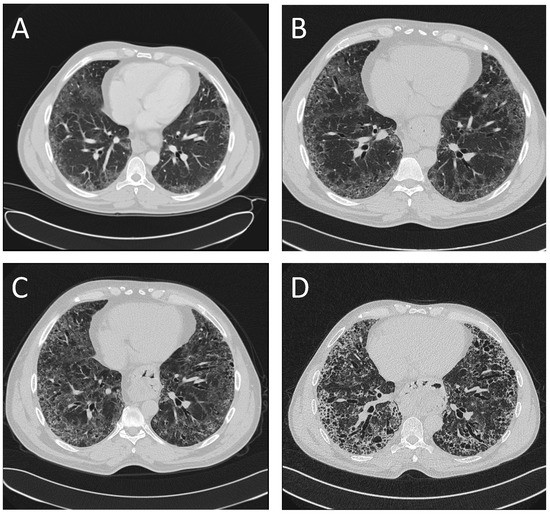

An Atypical Case of Idiopathic Pulmonary Fibrosis in a Patient from Africa

2. Case Presentation